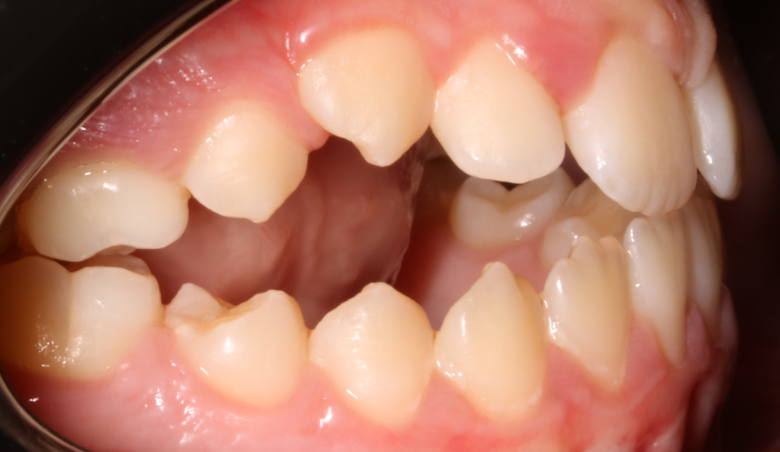

Llama la atención a primera vista la mordida abierta bilateral, especialmente pronunciada entre el cuadrante 1 y 4 debido a una interposición lingual en posición estática. Entre otros hallazgos fundamentales, observamos: un patrón dolicofacial severo (VERT: -2), una compresión de la arcada superior que cursa con un perfil y relación oclusal de clase III y la rotación del 35 y 45. Este caso se trató con un disyuntor, exodoncias de 44 y 34, brackets convencionales y educadores para rehabilitación de la lengua en un tiempo de 22 meses. Aunque estoy satisfecho con el resultado final, me hubiera gustado clavar la interscuspidación de premolares en el cuadrante I y IV, y mejorar la relación oclusal de cuadrante II y III. Sin embargo, lo bonito, es que hay a veces, en la ortodoncia real, que el paciente está satisfecho y quiere terminar antes de tiempo, o por el contrario, que el profesional intenta pero no consigue el resultado deseado. Y a mí más que compartir casos perfectos, me gusta mostrar mis errores, mi realidad.

La ilustración nos deja entrever algo tan fácil como que en un paladar pequeño no entra una lengua grande. Y viceversa, en un paladar grande entra una lengua grande. Llevándonos dicha explicación al caso que nos atañe, podemos ver  en la fotografía lateral del lado derecho como la lengua escapa y busca espacio, de manera permanente, entre el cuadrante 1 y 4,  estímulo que mantenido en el tiempo generó en una mordida abierta lateral.